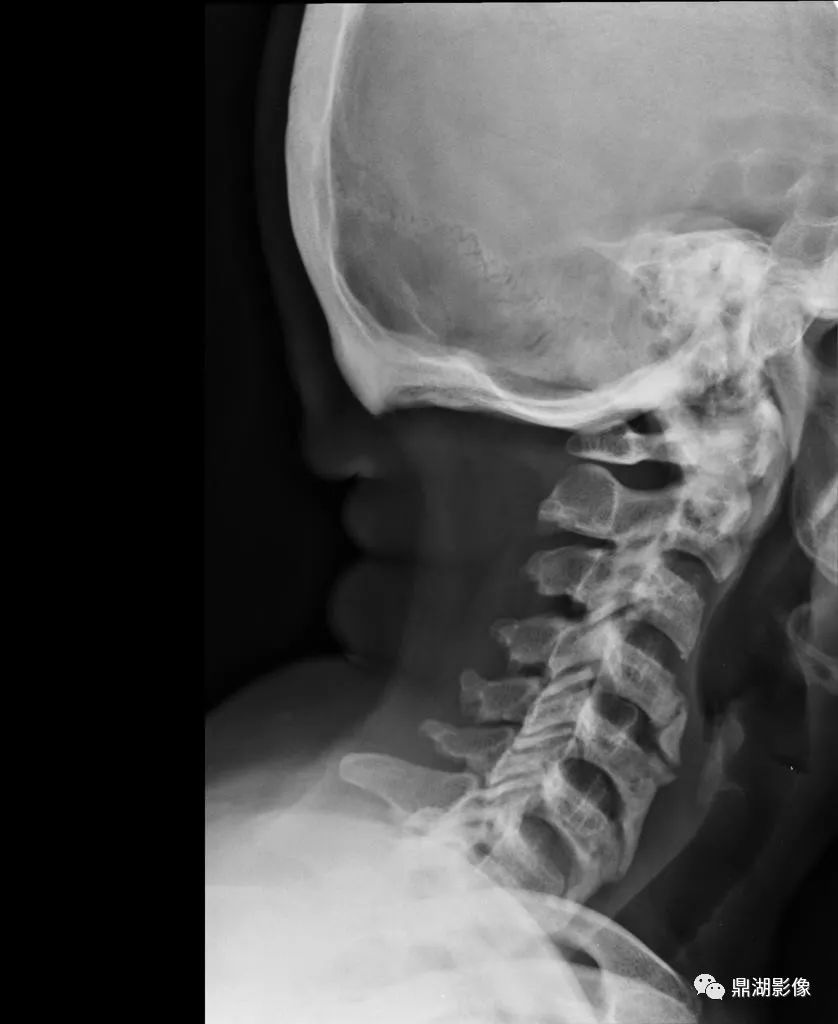

- 脊柱最常受累

- 胸椎最常见,其次为颈椎、腰椎

- 椎体前外侧连续性骨化,后纵韧带、黄韧带也可受累非边缘性韧带骨赘,即骨化不发生于间盘边缘,形成波浪样外观

- 椎间隙高度正常